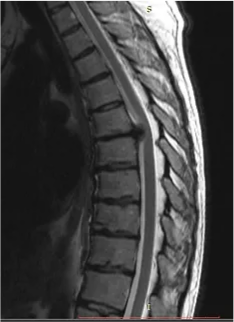

Грыжа грудного отдела позвоночника

Грыжа грудного отдела позвоночника представляет собой локальное смещение материала межпозвонкового диска грудного отедела позвоночника вне его пределов.

Для диагностики грыжи грудного отдела позвоночника используется МРТ (мощность магнита не ниже 1,5 Тесла, и обязательно записать на диск).